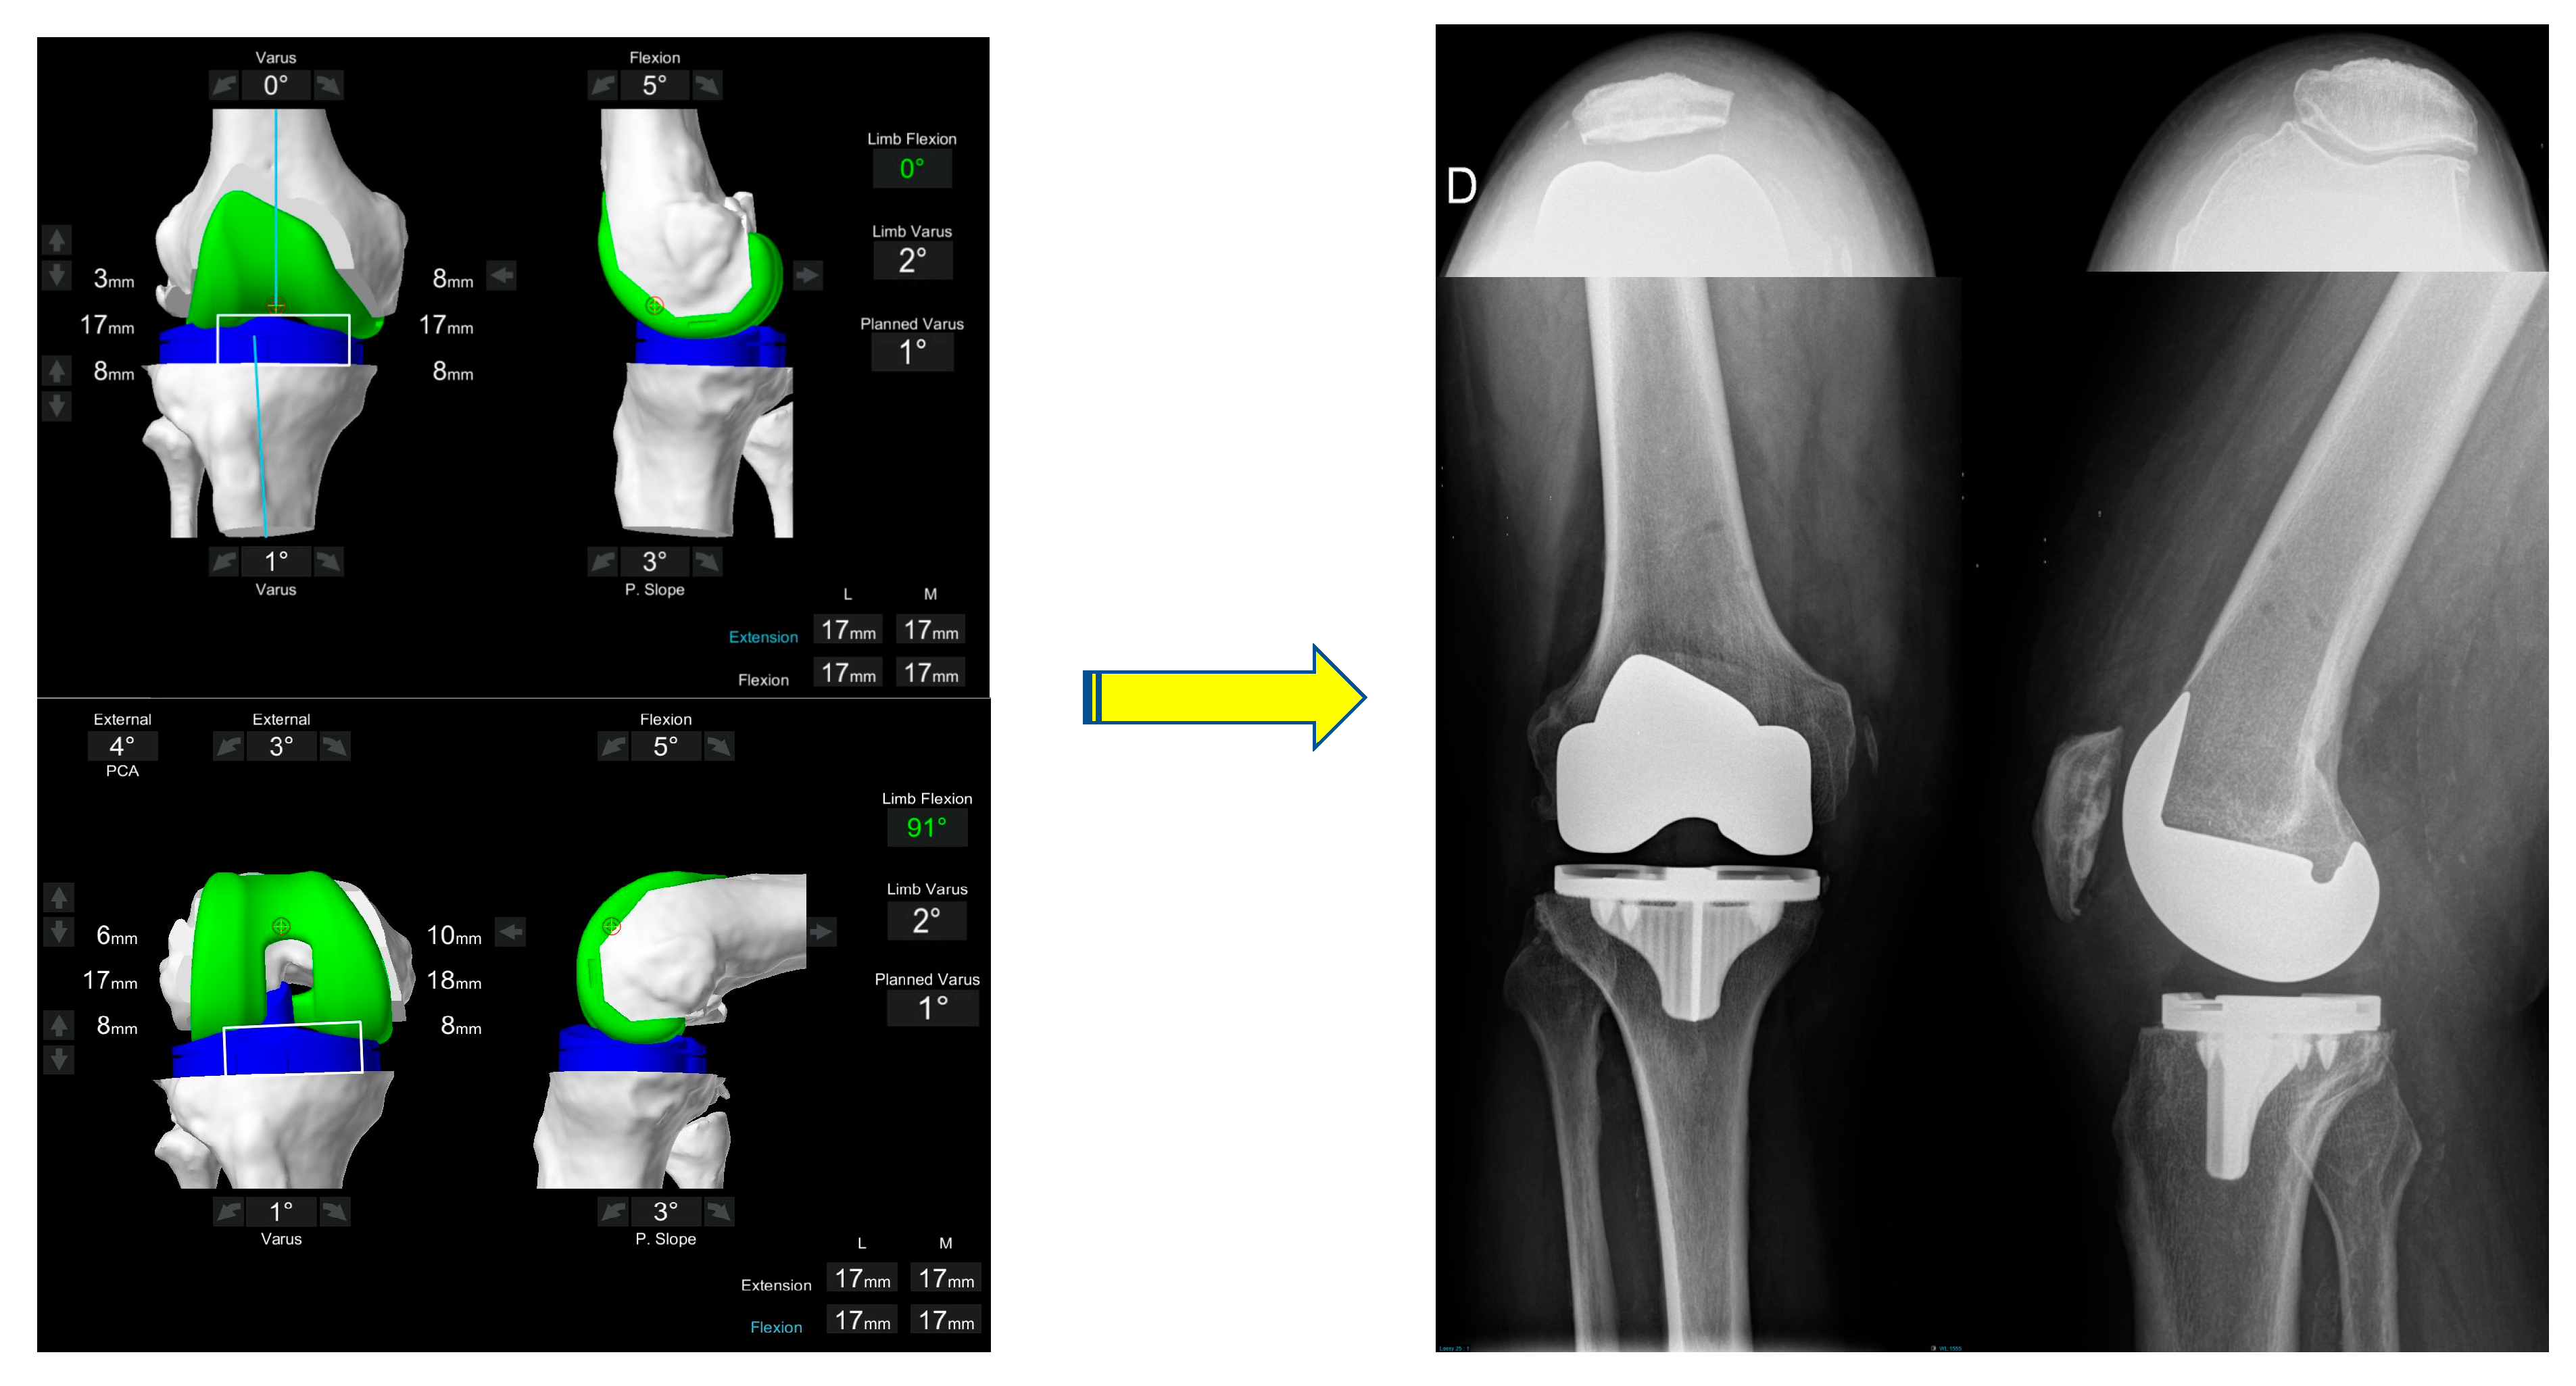

- Coronal plane: femoral implant positioning is planned according to the LDFA with an upper limit of 6° mechanical valgus in femur. To achieve a final alignment with a maximum valgus of 183°, varus positioning on the tibia may be required unless there is extra-articular varus deformity in either the femur or tibia.

- Axial plane: In the valgus morphotype, the posterior lateral femoral condyle is often deficient, making the posterior condylar axis an unreliable landmark for rotation [38]. For this reason, femoral component rotation is planned to balance the flexion space according to the transepicondylar axis (TEA), within a range of 3° internal rotation (IR) to 6° external rotation (ER) to balance the flexion gap. All these adjustments must be made while respecting the alignment with the trochlear groove; care must be taken to assess for trochlea dysplasia which may be present in valgus knees, and if so, recreation of the dysplastic anatomy, such as internally rotating the femur relative to the posterior condylar axis (PCA), should be avoided.

- Resection depth: For distal femoral resection, the medial femoral condyle represents the reference point. A smaller amount of bone is typically removed from the lateral femoral condyle because of wear and morphological variation that is encountered here. It is 9 mm resection if planned from the medial distal femoral condyle and typically 4-6mm from the lateral femoral condyle. The target of 9 mm resection is based on 7 mm of bone plus 2 mm of cartilage.

- Size: The tibia is initially sized with rotation to 0° on the axial view of the CT scan with the aim of having maximal cortical contact with no implant overhang.

- Coronal plane: tibial implant position is aligned to provide the closest match to the medial proximal tibial axis (MPTA) and balance flexion and extension gaps in a range from 2° of valgus to 6° of varus. In the valgus morphotype, in order to avoid a residual valgus HKA > 3° valgus, the tibia is often cut orthogonal to its mechanical axis. A valgus tibial position more than 2° should be avoided. Valgus tibial positioning is reserved for cases where the deformity is an extra-articular tibial deformity, which in our experience is uncommon.

- Sagittal plane: tibial implant position is set to match the patient’s native posterior tibial slope with a limit of 3° when using a PS implant and can be modified to balance the flexion gap if necessary. A limit of 10° combined femoral-tibial flexion is allowed.

- Axial plane: tibial implant is positioned using Akagi’s line. Particular attention should be paid to the avoiding IR of the tibial component, as the valgus morphotype tibia typically falls into ER in deep flexion [36,37] (the position the implant is placed), which promotes the error of internally rotating the tibial baseplate during trials and implantation.

- Tibial resection: 8 mm resection is planned from the medial tibial plateau (6 mm bone + 2 mm cartilage) based on subchondral bone and an average cartilage depth of 2 mm in the normal knee, to use a 9 mm polyethylene insert. Resection from lateral tibial plateau is, typically less i.e., 4–6mm due to wear, but also to account for the extra articular tibial valgus deformity that often co-exists in the valgus morphotype [31]. This gives a combined planned resection of 17 mm medially, which is the combined thickness of this implant with its thinnest tibial liner.